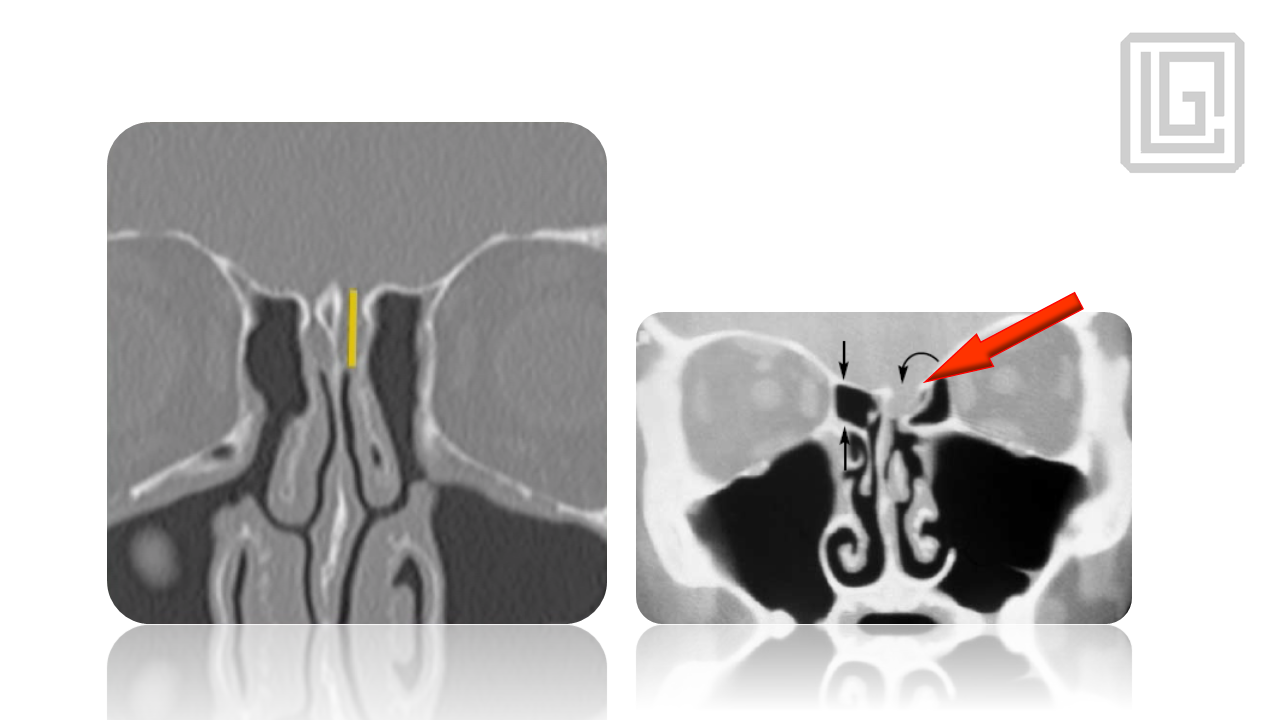

In-depth presentation on the pathophysiology of chronic rhinosinusitis, radiologic planning, sinonasal anatomy, and step-by-step FESS surgical protocol. Covers infundibulum, osteomeatal complex, surgical landmarks, instrumentation, complications, and postoperative management. Presented by Dr. Levon Galstyan.